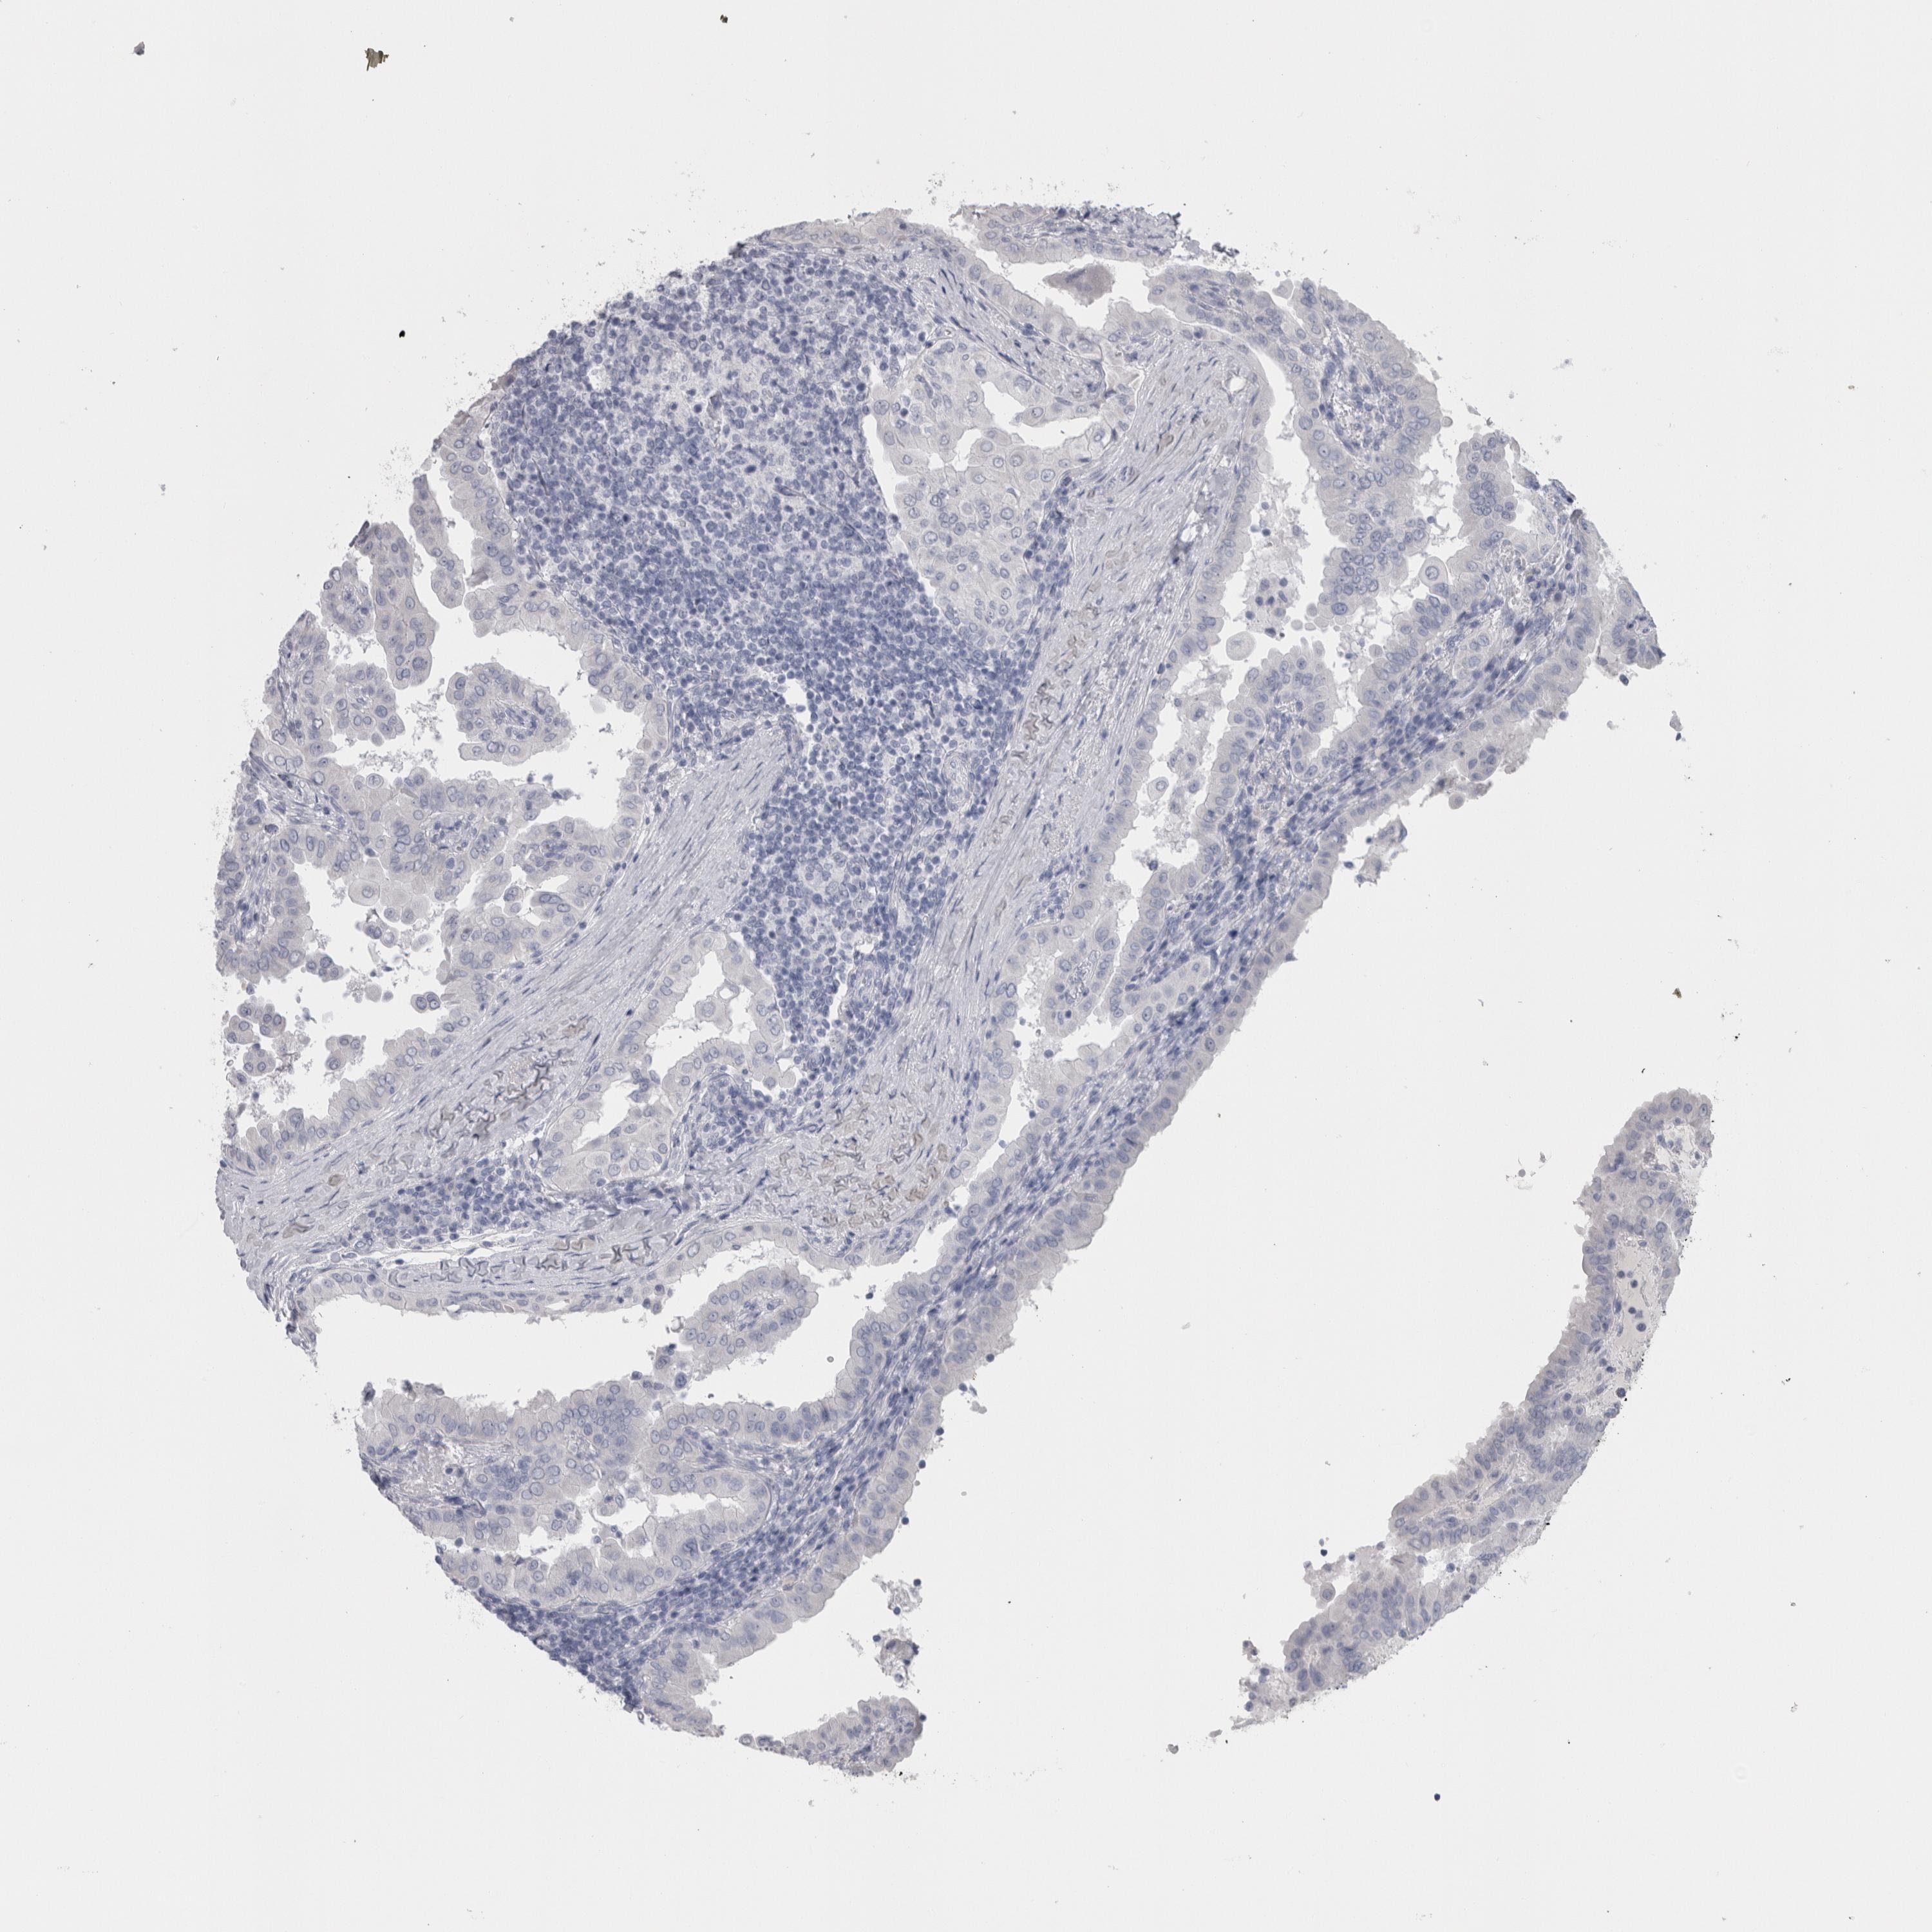

THYROID CANCER - Protein expressioni

A mouse-over function shows sample information and annotation data. Click on an image to view it in a full screen mode. Samples can be filtered based on level of antibody staining by selecting one or several of the following categories: high, medium, low and not detected. The assay and annotation is described here.

Note that samples used for immunohistochemistry by the Human Protein Atlas do not correspond to samples in the TCGA dataset.

Antibody stainingi

Antibody staining in the annotated cell types in the current human tissue is reported as not detected, low, medium, or high, based on conventional immunohistochemistry profiling in selected tissues. This score is based on the combination of the staining intensity and fraction of stained cells.

Each image is clickable and will lead to virtual microscopy that enables deeper exploration of all samples and also displays staining intensity scores, fraction scores and subcellular localization as well as patient and tissue information for each sample.

Antibody HPA051257

Antibody CAB026357

Staining

High

Medium

Low

Not detected

Intensity

Strong

Moderate

Weak

Negative

Quantity

>75%

75%-25%

<25%

None

Location

Nuclear

Cytoplasmic/membranous

Cytoplasmic/membranous,nuclear

Papillary adenocarcinoma, NOS

Follicular adenoma carcinoma, NOS